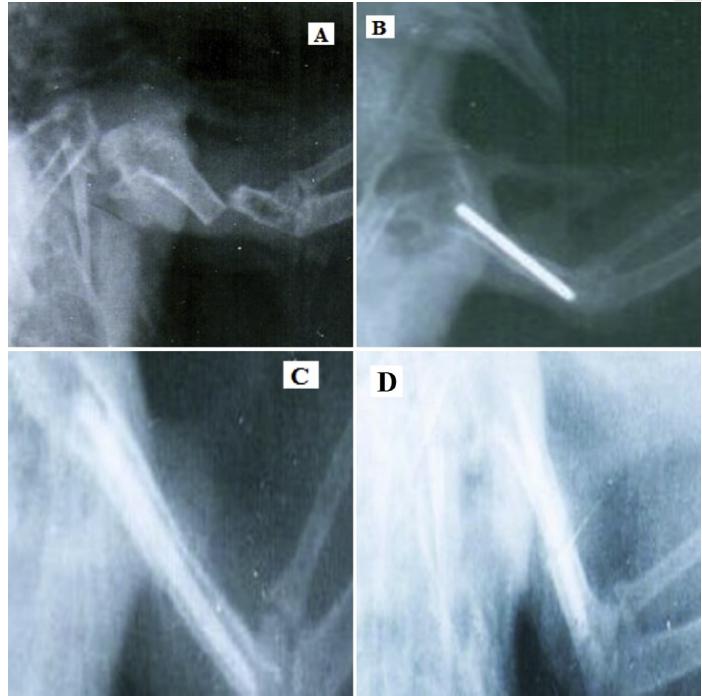

Sheep and dog bones can be whittled into orthopedic pins that stabilize pigeons' fractured wings, helping the fractures to heal properly without follow-up surgery. Researchers describe the treatment, which is cheaper and more efficient than using metal pins for pigeon rehabilitative surgeries, November 20th in the journal Heliyon .

Nazhvani's team thought bones could be the answer. They sanded and processed sheep and dog bones, obtained from animals that had previously died, into pins small enough to be inserted into a pigeon's humeral bones--the wing bone closest to a bird's body. After 32 weeks of observation, pigeons with sheep or dog bone orthopedic pins were able to fly as well as before the operation.

"There was no rejection of any of the implanted bones at all," says Nazhvani. "And for pigeons who underwent the treatment, there was early function of the wing and more solid repair than we thought due to slow absorption of the implant and its contribution to the healing process."